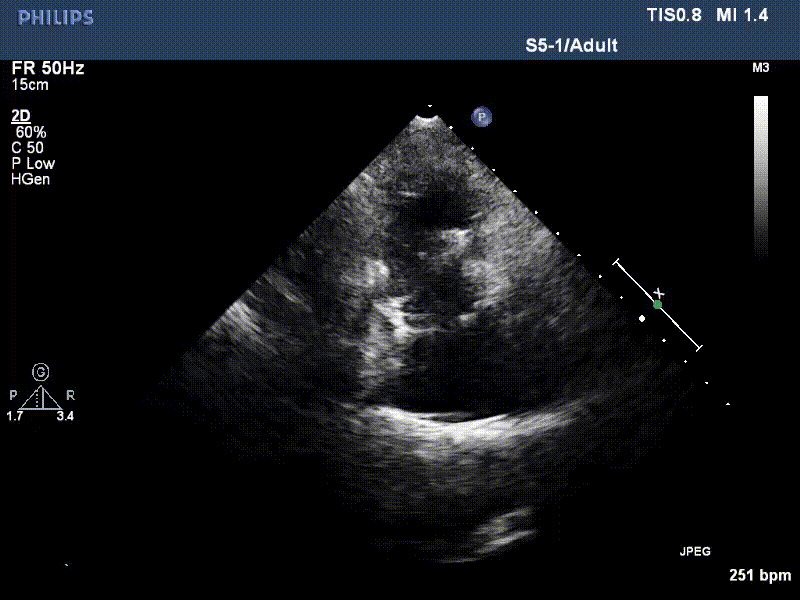

流并分別伴有房顫和房撲,高外科手術(shù)風(fēng)險(xiǎn)。術(shù)前超聲提示,兩例患者下腔靜脈寬度分別為13mm和29mm,右房?jī)?nèi)徑(上下徑和左右徑)分別為52×41mm和53×43mm,彩色多普勒顯示極重度三尖瓣反流,VCW分別為14×15mm和10mm。

1年前,兩例患者因難治性雙下肢水腫輾轉(zhuǎn)多家醫(yī)院尋求救治,考慮到兩例患者高齡、基礎(chǔ)疾病多、STS評(píng)分高,不適合傳統(tǒng)外科開(kāi)胸手術(shù),葛均波院士及其團(tuán)隊(duì)周達(dá)新教授、潘文志教授、張?jiān)床┦俊㈥惿┦俊㈥惖さげ┦?/strong>聯(lián)合心外科王春生、魏來(lái)主任,麻醉科繆長(zhǎng)虹、郭克芳主任以及心超室的潘翠珍教授、李偉教授共同討論決定,采用我國(guó)創(chuàng)新器械LuX-Valve Plus經(jīng)血管三尖瓣置換系統(tǒng)為患者進(jìn)行手術(shù)。相較于第一代產(chǎn)品LuX-Valve,LuX-Valve Plus經(jīng)血管三尖瓣置換系統(tǒng)對(duì)輸送系統(tǒng)進(jìn)行了全面升級(jí),實(shí)現(xiàn)了經(jīng)頸靜脈入路的方式,進(jìn)一步減小了手術(shù)風(fēng)險(xiǎn)和對(duì)患者的創(chuàng)傷。目前隨訪(fǎng)1年心超結(jié)果顯示,三尖瓣極重度反流消失,人工三尖瓣瓣膜穩(wěn)定牢固,瓣葉活動(dòng)度良好,右心室及下腔靜脈明顯縮小,心輸出量增加。兩位老人手術(shù)后沒(méi)有出現(xiàn)過(guò)胸悶氣促的癥狀,下肢水腫緩解,活動(dòng)耐力提升,生活質(zhì)量也大為提高。

圖2 患者植入LuX-Valve Plus后,1年隨訪(fǎng)心超提示無(wú)三尖瓣反流